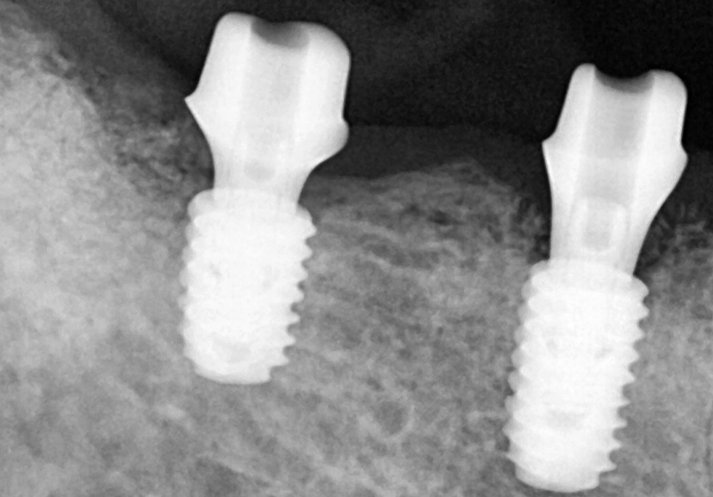

임플란트가 잇몸뼈에 잘 고정될 수 있도록

충분한 시간을 기다려주었고,

크라운 (보철물) 작업을 위하여

맞춤형 지대주를 체결한 모습입니다.